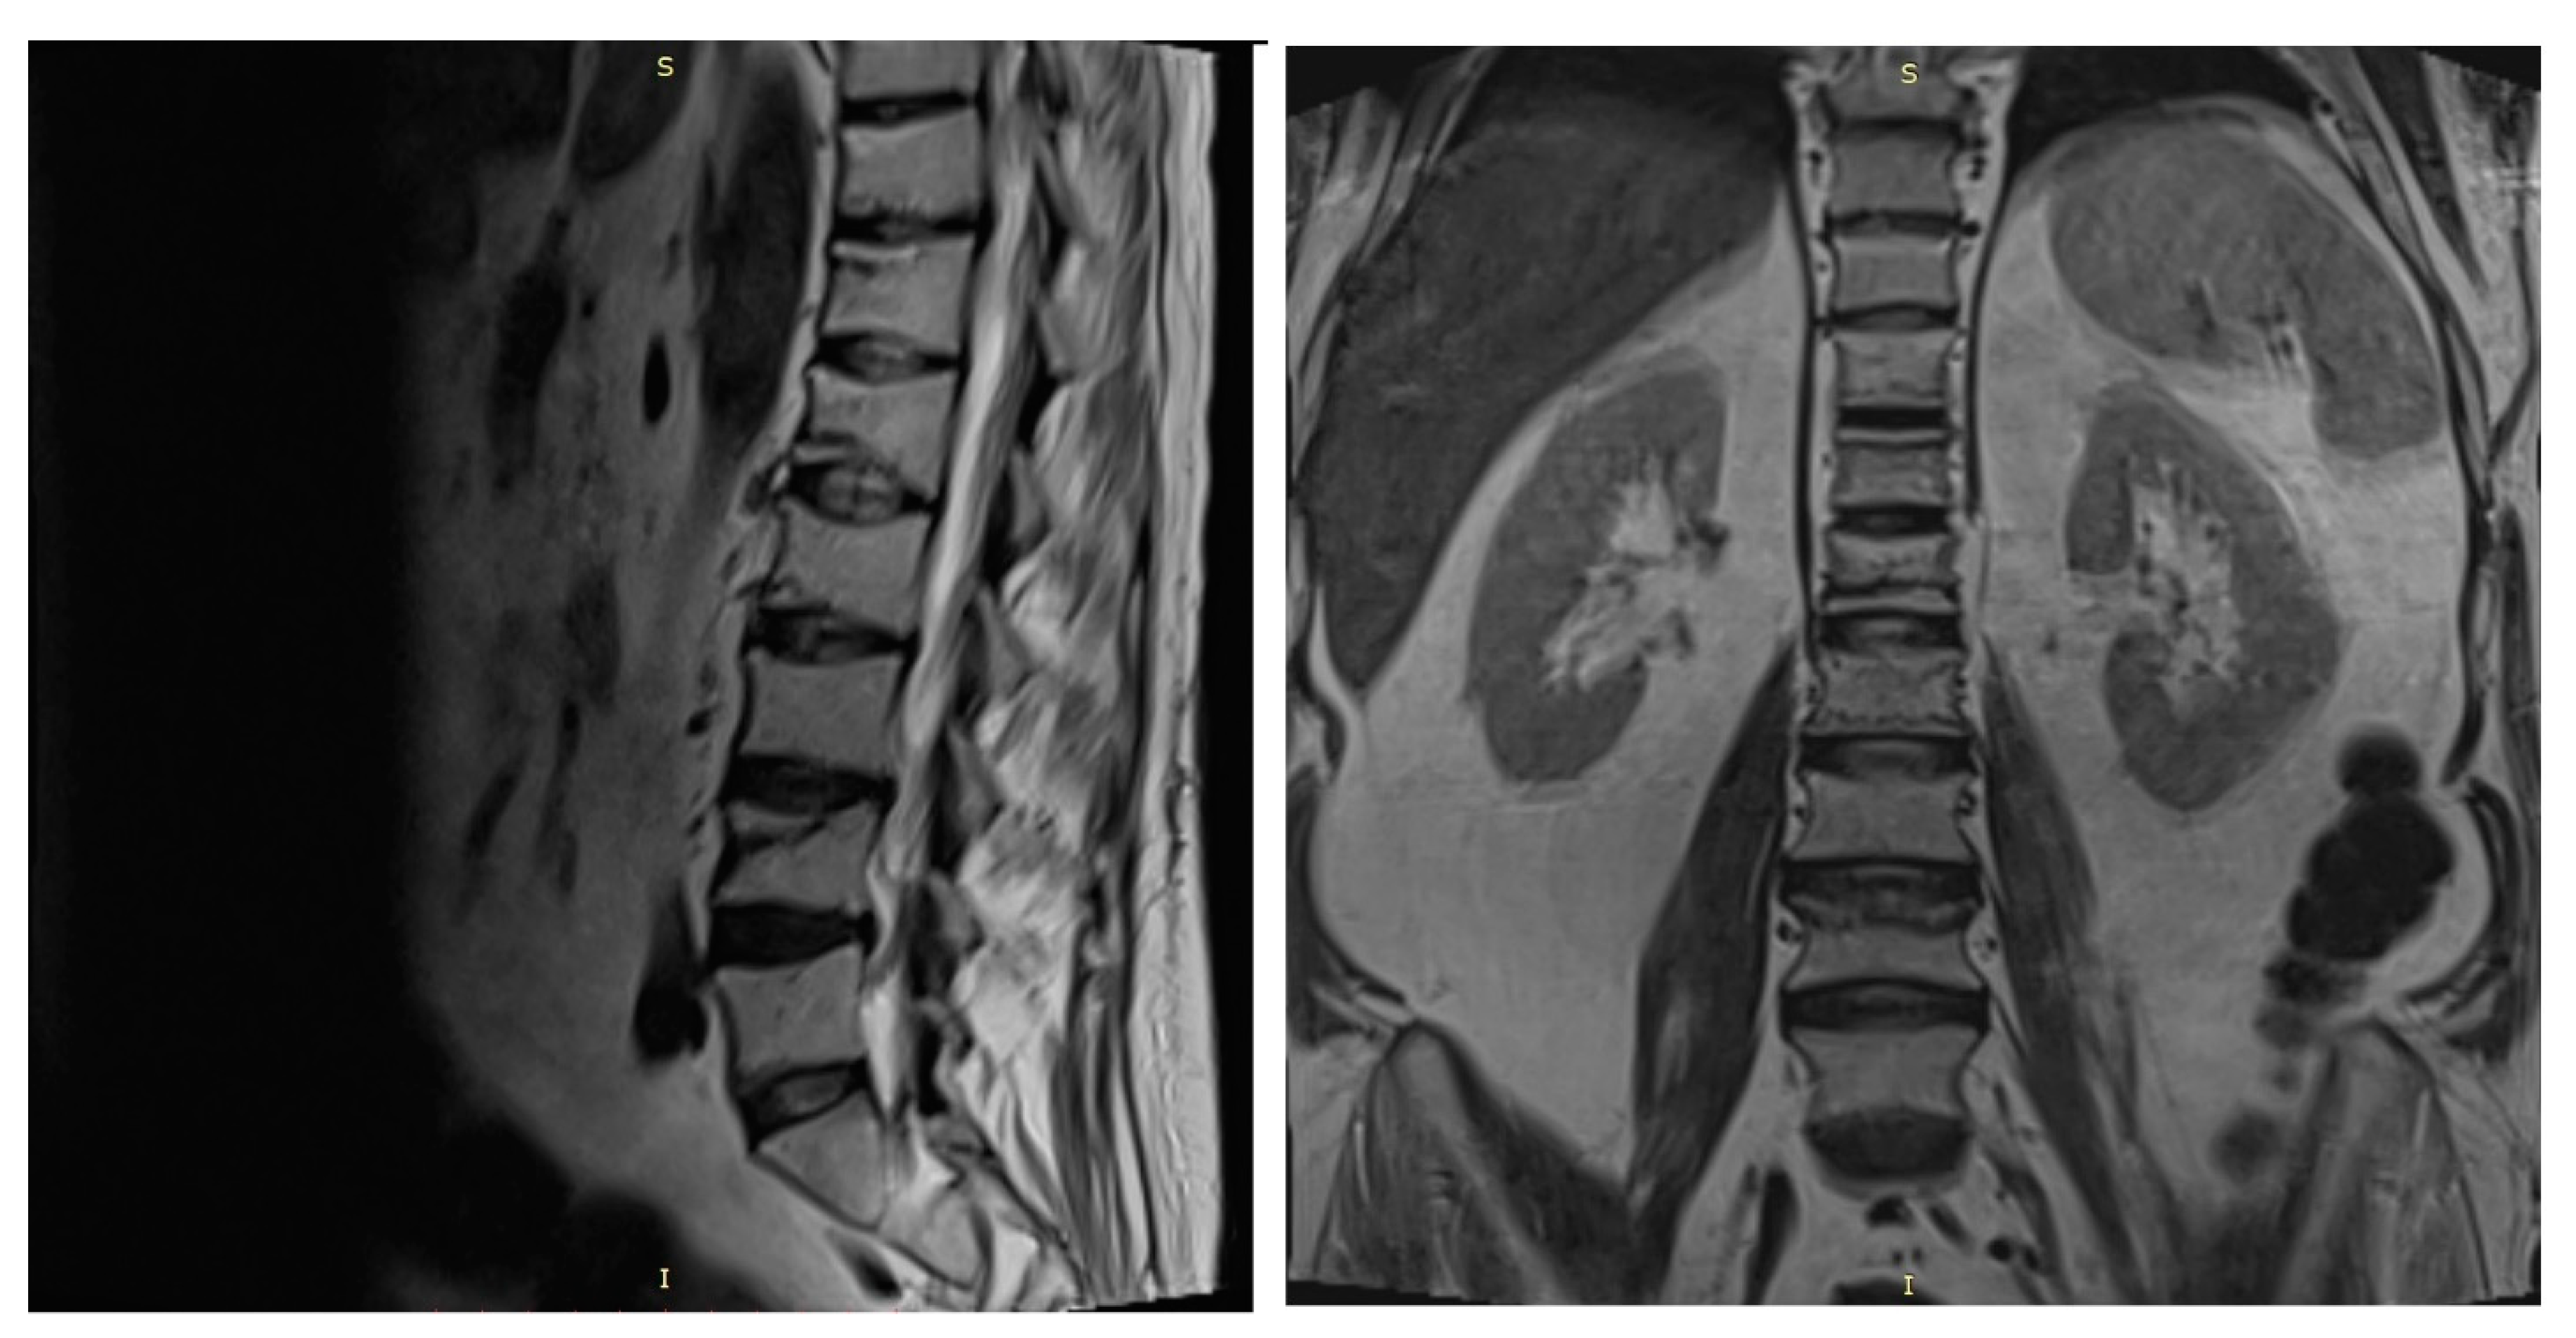

A spine MRI exposed multiple vertebral fractures at T11, T12, L1, L2 and L4 levels and no osseous spinal metastases (Figure 4). As dual energy X-ray absorptiometry (DXA) also displayed a low bone mineral density for his age (right total hip Z score = −2 SD), the patient was diagnosed with severe secondary glucocorticoid-induced osteoporosis and received treatment with intravenous zoledronic acid.

Figure 4. Spine MRI showing T11, T12, L1, L2 and L4 vertebral fractures. (s = superior, I = inferior).